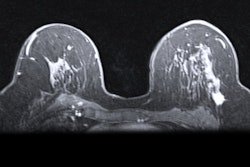

3 MRI features tied to DCIS surgical success

In another presentation, Chou described how her team analyzed results from a prospective, multicenter trial evaluating the use of MRI for ductal carcinoma in situ (DCIS). The team identified three MRI features that could help predict outcomes for surgical treatment of DCIS.

The team found lesion size on preoperative MRI was tied to the success of single wide local excision in their study of 399 women with DCIS. Successful surgeries had a median lesion size of 17 mm on MRI, compared with an average size of 24.5 mm for unsuccessful surgeries.

In addition, cancers with a low or intermediate nuclear grade on biopsy were associated with surgical success, compared with cancers with a high nuclear grade. Lesions with focal distribution of nonmass enhancement (NME) also had better success rates than those with segmental or other NME distributions.

"These results suggest that MRI features may be used to predict surgical success rates," Chou said.